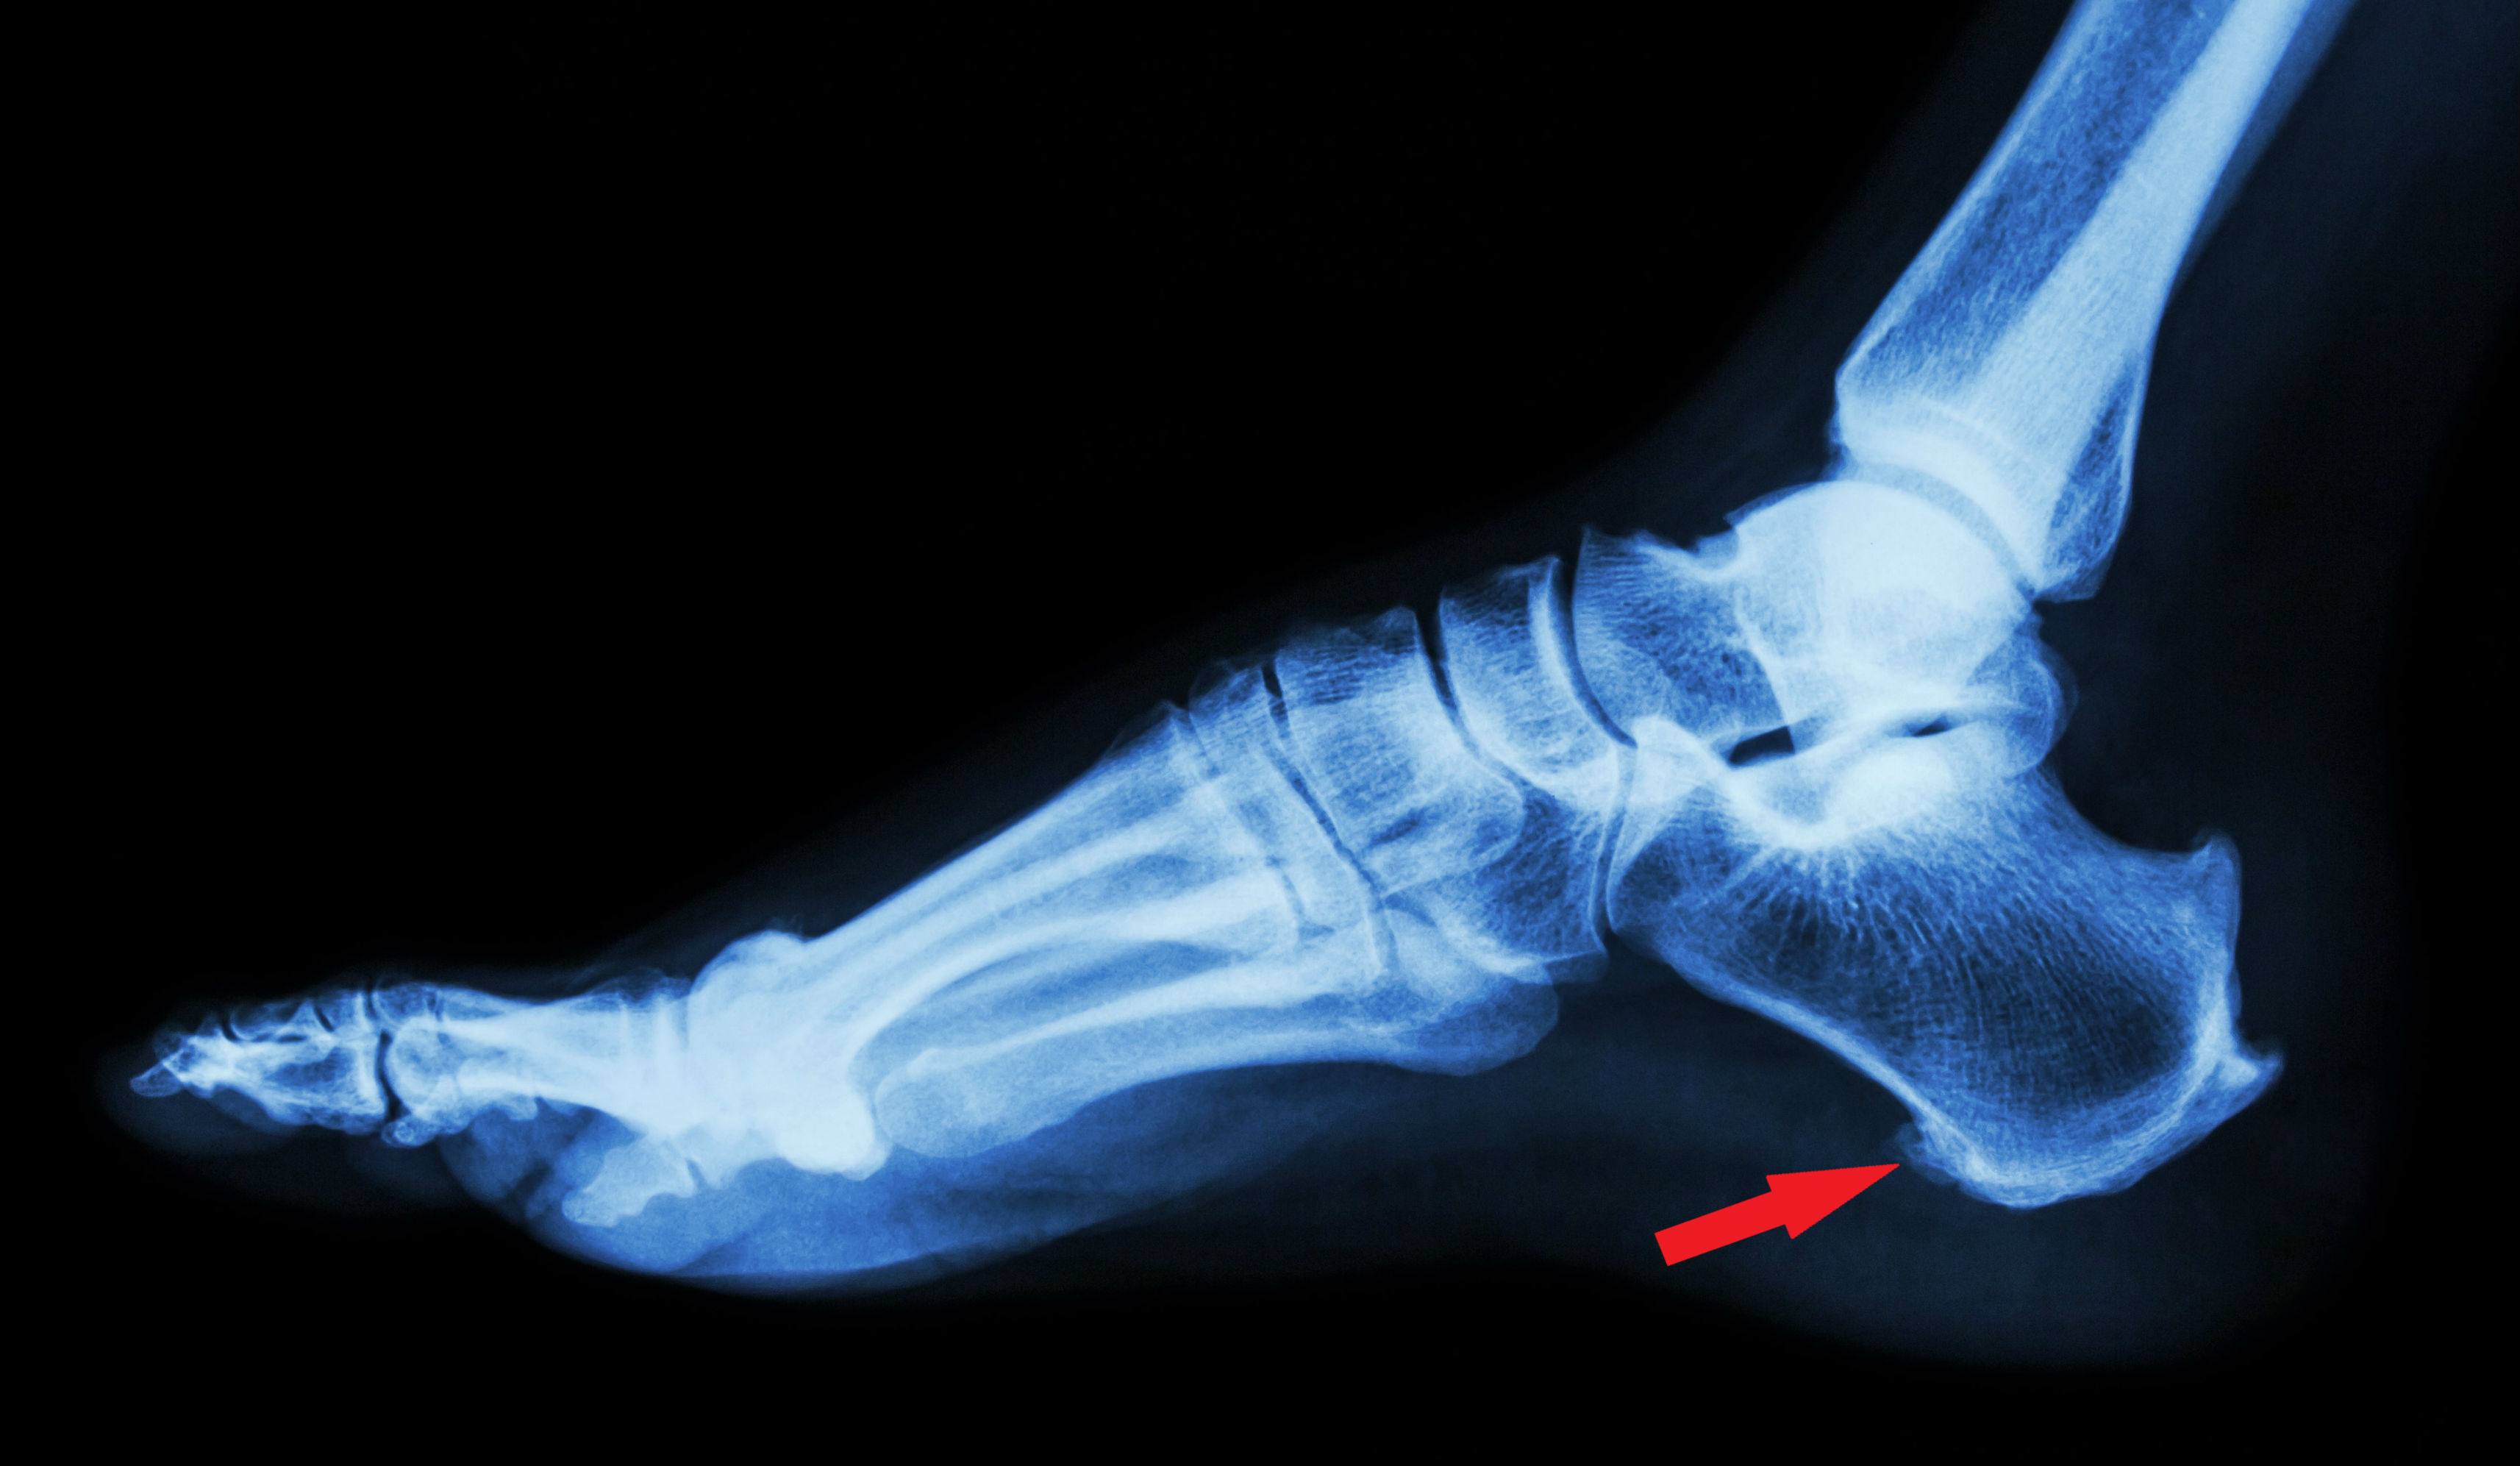

Hvorfor hedder det hælspore?

Diagnosen 'hælspore', stammer i virkeligheden fra beskrivelsen af røntgenbilleder taget af patienter med symptomer. På røtgenbillederne kan man ofte se en lille 'udtrækning' af hælknoglen fortil, hvor svangsenen sidder fast. Det ligner på røntgenbilleder en lille 'spore', deraf navnet. Man troede engang, at det var denne spore, der var årsag til alle symptomerne.

Det har imidlertid vist sig, at der ikke er nogen klar sammenhæng mellem det at have en hælspore og det at have symptomer. Rigtig mange har symptomer men ingen hælspore på deres røntgenbilleder, mens der er mange, der har en hælspore, men aldrig symptomer. Så man kan som udgangspunkt ikke stille diagnosen ud fra et røntgenbillede. Men, i nogle tilfælde skal man bruge et røntgenbillede til at udelukke en eventuel anden lidelse.